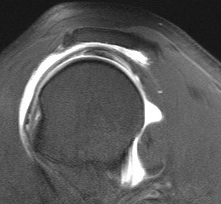

Axial MRI Sagittal MRI

Axial MRI with meso-acromiale